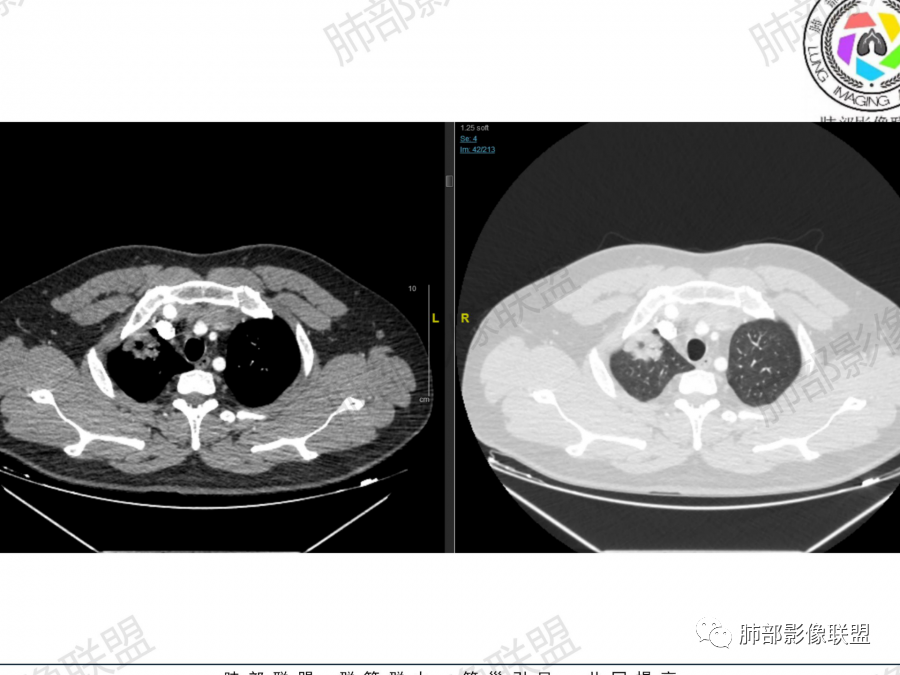

1、青年男性、咳嗽气喘一月,加重两天入院。实验室检查:有铁蛋白增高,血脂、肝功异常、有免疫异常。

2、右肺多发结节影,大者位于右肺上叶尖段,内可见空洞,空洞内壁欠规整,内可见分隔,余结节位于胸膜下、结节大小不等、形态相近,强化均匀,内部可见血管穿行,血管及支气管走行自然。结合临床及影像,符合隐球病。

1、肺隐球菌病影像学分为4类表现:

孤立结节型:位于胸膜下,两下肺多见、上肺偏少。

大片实变型:多为下叶单叶胸膜下。

多发结节或实变型:分布多为下叶单叶胸膜下、少数两肺多发、多叶段分布。弥漫型:本例为单侧肺、多叶结节型。

(1)结核球,结节内钙化常见,边缘光整,少见“晕征”,卫星灶多形、多灶,往往位于主病灶周围。

(2)空洞性肺癌,空洞内壁凹凸不平,见壁结节,典型者边缘见分叶、毛刺,易鉴别。

(3)淋巴瘤,往往伴有纵隔淋巴结增大,病灶内穿行血管欠自然且强化较隐球菌明显。